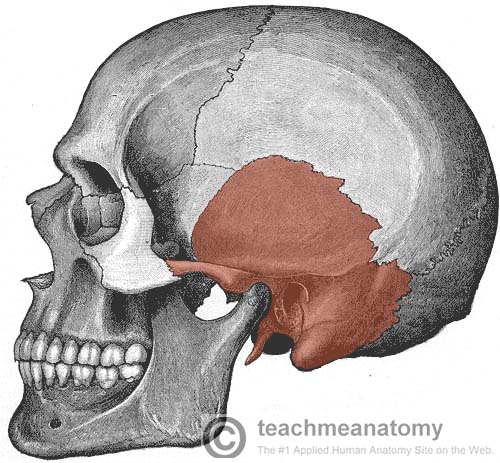

What is this region?

Temporal Bone